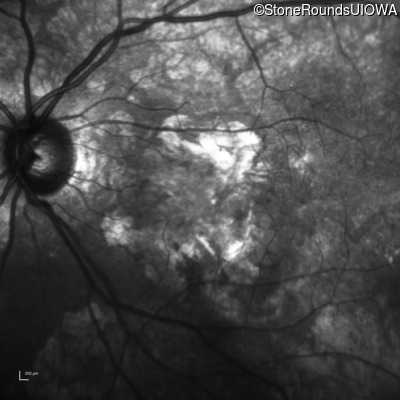

Age at visit: 64 years

OD OS

This 64 year old woman first noticed some distortion in her vision at age 46 while looking at graph paper.